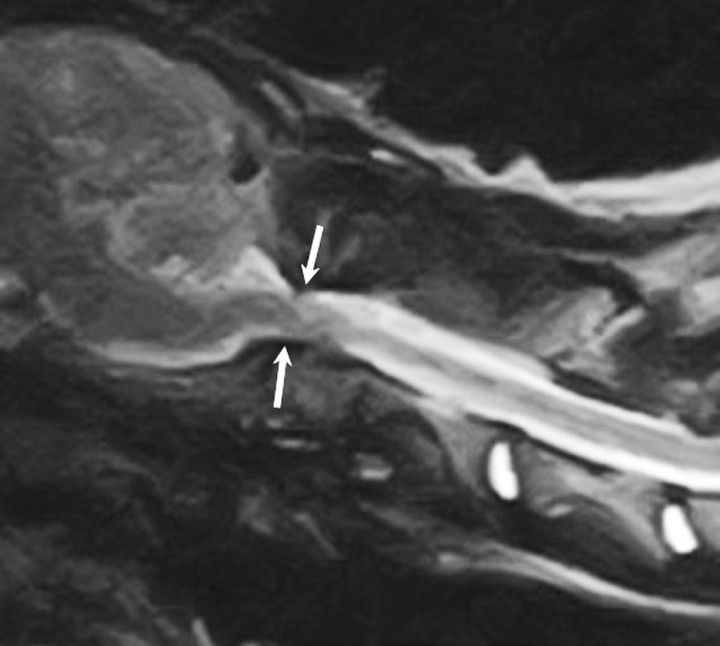

Es referida para evaluación neurológica una perra mestiza de 4 meses de edad y 23 kilos de peso por presentar dolor cervical y tetraparesia de 4 días de evolución tras sufrir un traumatismo. En la exploración física se palpó una asimetría del atlas, que parecía rotado, lo que hacía que el paciente sufriese una desviación severa del cuello con gran dolor a la manipulación. El examen neurológico reveló tetraparesia ambulatoria severa con retraso simétrico de las reacciones posturales en las cuatro extremidades. Los reflejos medulares y la evaluación de los pares craneales eran normales. Este examen fue compatible con una afección focal o difusa de los segmentos medulares C1 - C5. El diagnóstico diferencial, teniendo en cuenta la historia clínica y la exploración física, incluyó principalmente procesos de carácter malformativo, sin poder descartarse enfermedades traumáticas, inflamatorias o neoplásicas. Se realizaron radiografías de la columna cervical en proyección lateral y ventrodorsal donde se apreció una inestabilidad de la articulación AA evidenciada por aumento de distancia entre la lámina del atlas y la apófisis espinosa del axis (Fig. 1A). Sin embargo, el hallazgo más relevante consistió en la ausencia del ala (apófisis transversa modificada) y la mitad izquierda del cuerpo del atlas (Fig. 1B). Posteriormente se procedió a la realización de una tomografía computarizada (TC) donde se confirmó la existencia de una malformación cervical con desplazamiento rostral del axis, que hacía que el diente del axis sobrepasase el límite craneal del cuerpo del atlas y los cóndilos del occipital, quedando en contacto con el aspecto ventral de la médula oblonga (signo radiológico denominado “invaginación basilar” en medicina humana) (Fig. 2, A y B). El atlas presentaba una agenesia de su mitad izquierda y en su lugar se apreciaron dos pequeños núcleos óseos independientes que ocupaban una posición dorsolateral izquierda no unidos con el resto de estructuras óseas (Fig. 2, C). Aunque el arco derecho del atlas quedaba íntimamente asociado con el cóndilo derecho del occipital, se evidenció una conformación atlanto-occipital derecha normal, con una línea articular bien formada pero rotada (Fig. 2, B). En el aspecto ventral del atlas se observaba el “intercentrum” 1, así como la sincondrosis neurocentral derecha (Fig. 2, B). Sin embargo, la sincondrosis neurocentral izquierda y la dorsal no podían ser evidenciadas debido a la ausencia del centro de osificación del arco neural izquierdo (Fig. 2, C). Todas estas alteraciones hacían que la articulación atlanto-occipital quedase rotada, haciendo que la cabeza girase en contra del sentido de las agujas del reloj visto desde un plano dorsal (Fig. 3, A y B). El agujero vertebral lateral y el agujero transverso del arco derecho del atlas estaban correctamente formados (Fig. 3, A). Por otro lado, se apreció como el aspecto craneal del cuerpo del axis y la apófisis odontoides estaban deformados, engrosados e hiperostóticos (Fig. 2, A). El borde craneal de la apófisis espinosa del axis quedaba deformado con desviación derecha, haciendo leve prominencia sobre el atlas (Figs. 2A y 3A). Posteriormente, se decidió realizar una resonancia magnética de la columna cervical para valorar el parénquima medular, donde se evidenció una severa compresión dorsoventral de la médula espinal a nivel de la articulación AA con obliteración del espacio subaracnoideo ventral y dorsal (Fig. 4). Las secuencias ponderadas en T2 demostraron la hiperintensidad del parénquima medular en el punto de mayor compromiso (Fig. 4).

<p>Imagen sagital ponderada en T2 obtenida mediante RM de la columna cervical. Véase el compromiso medular a nivel de la articulación atlantoaxial, marcado por una obliteración del espacio subaracnoideo ventral y dorsal (flechas), lo cual produce una desviación sigmoidea del cordón medular.</p>

Figura 4

Imagen sagital ponderada en T2 obtenida mediante RM de la columna cervical. Véase el compromiso medular a nivel de la articulación atlantoaxial, marcado por una obliteración del espacio subaracnoideo ventral y dorsal (flechas), lo cual produce una desviación sigmoidea del cordón medular.